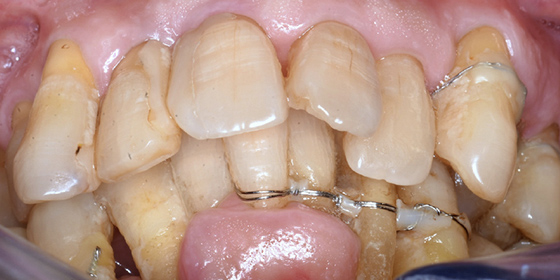

治療前

この症例では下顎の歯周病が特に進行していて、歯がクラグラで噛みにくい為、下の歯を抜歯してオールオン4で治療、上は特に歯周病が進行している左側の大臼歯を抜歯して経過観察することにしました。